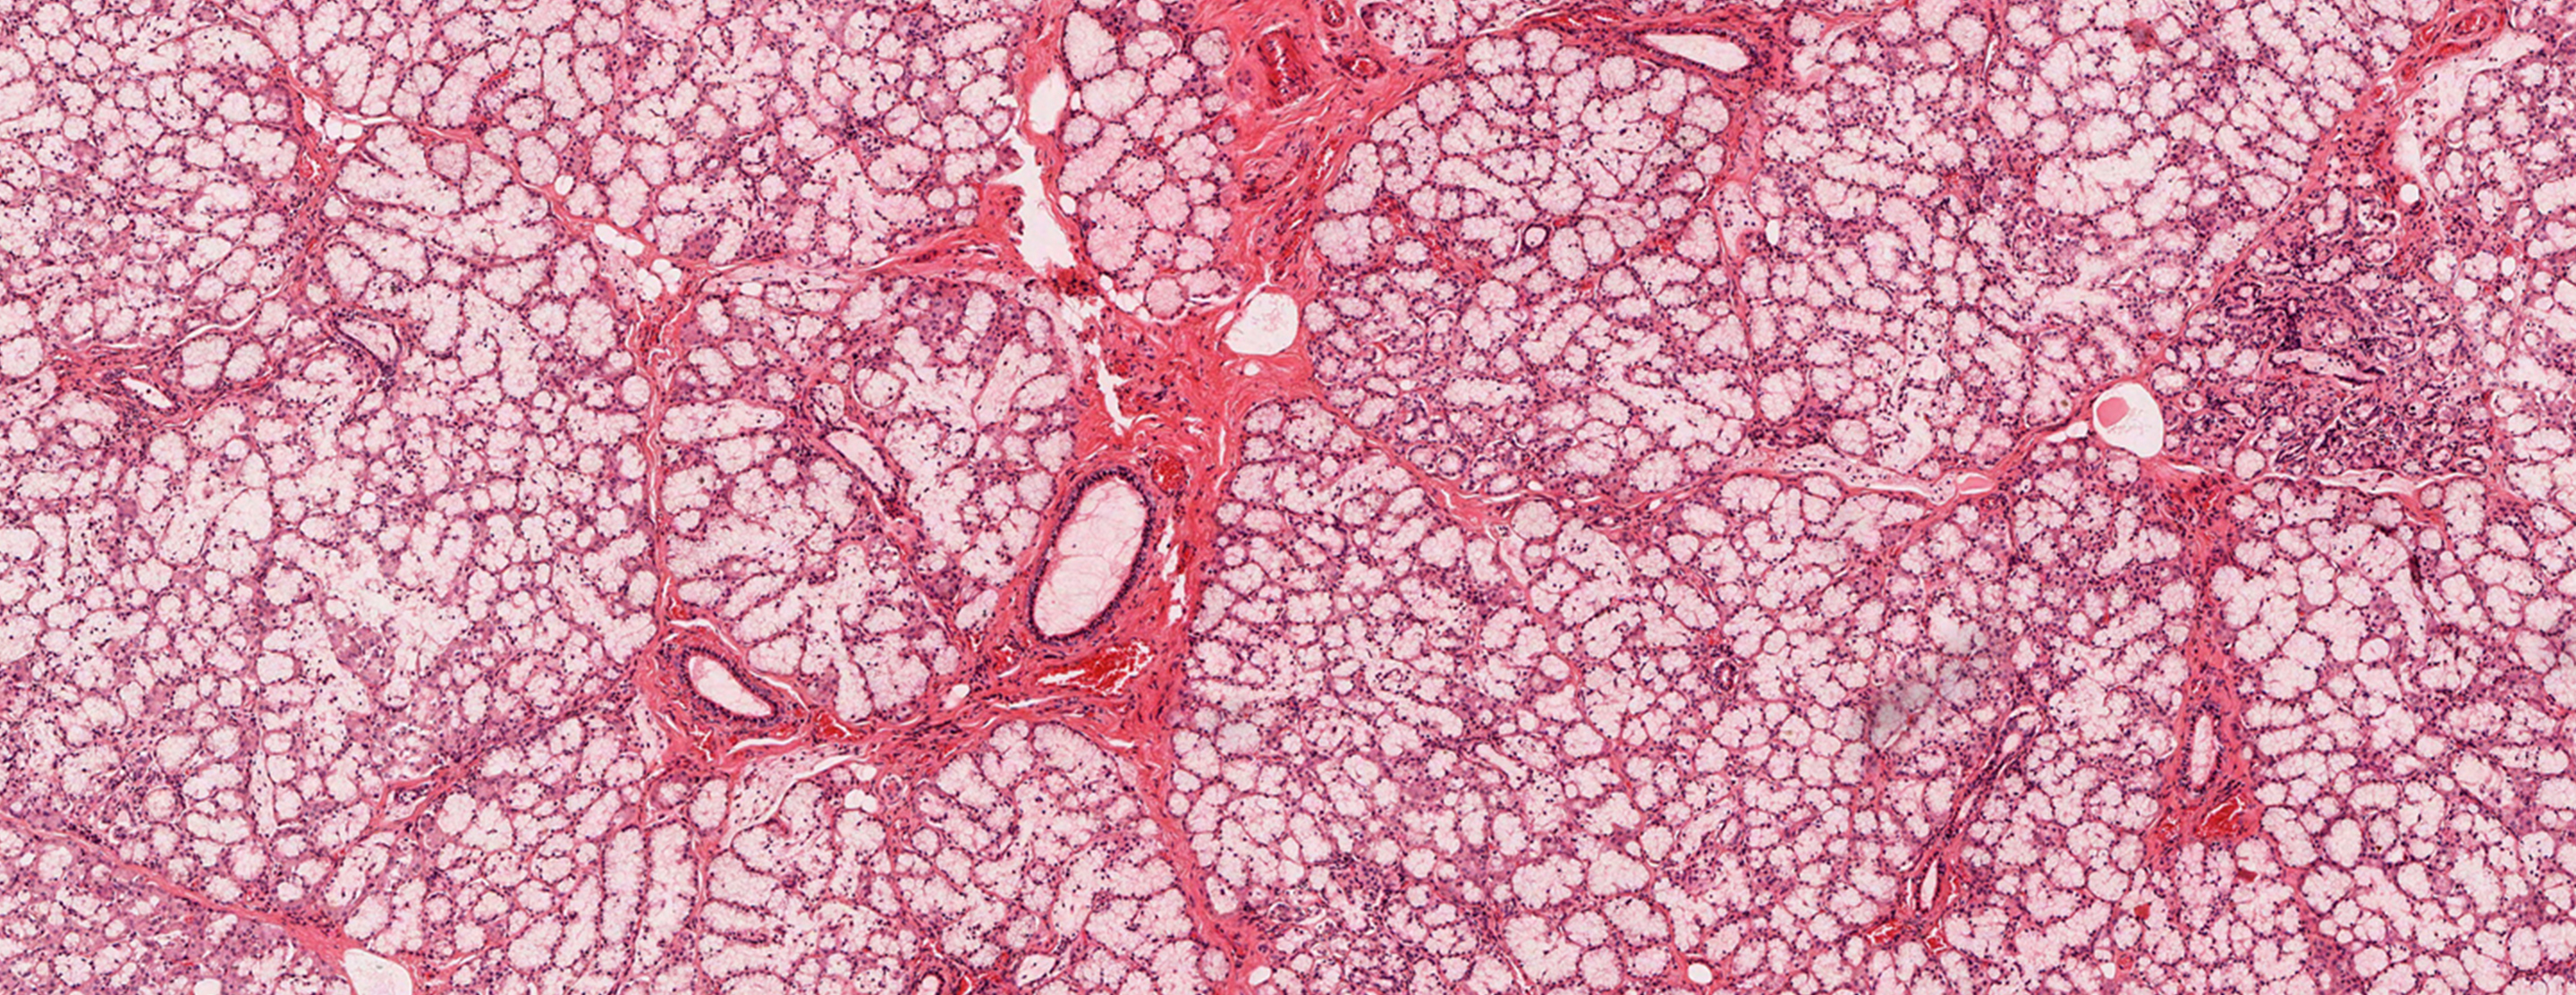

An oropharynx lesion biopsy is surgery in which tissue from an abnormal growth or mouth sore is removed and checked for disease.

All or part of the problem area (lesion) is removed. It is sent to the laboratory to check for diseases. If a growth in the mouth or throat needs to be removed, the biopsy will be done first. This is followed by the actual removal of the growth.

Abnormal results may mean:

Cancer (such assquamous cell carcinoma )- Benign lesions (such as papilloma)

- Fungal infections (such as candida)

Histoplasmosis Oral lichen planus - Precancerous sore (leukoplakia)

- Viral infections (such as Herpes simplex)